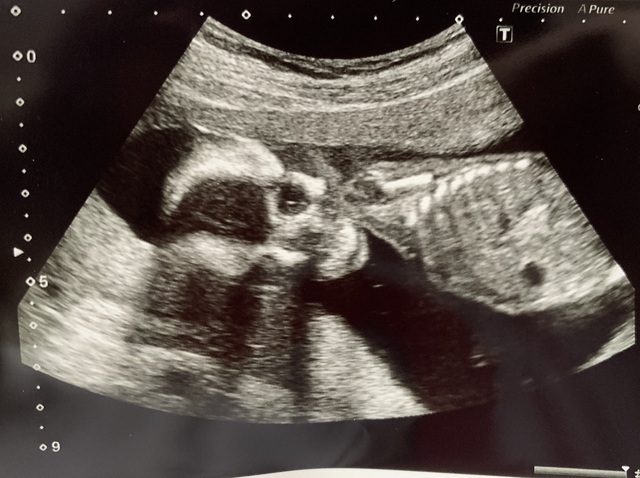

17週6日(17w6d・男の子)|みこっちゆうきっち さん(36歳)

エコー写真撮影時のエピソード:

このくらいの週数からつわりが治り、次の日から夫と一泊温泉旅行に行くために念のため健診に行きました。

毎回お顔をこっちに向けて見せてくれるので今回もとても楽しみにしていたら、なんと指をしゃぶっておっぱいを吸う練習をしていました!

こんな事までできるようになったんだなぁと夫婦とてもうれしかったのを覚えています!